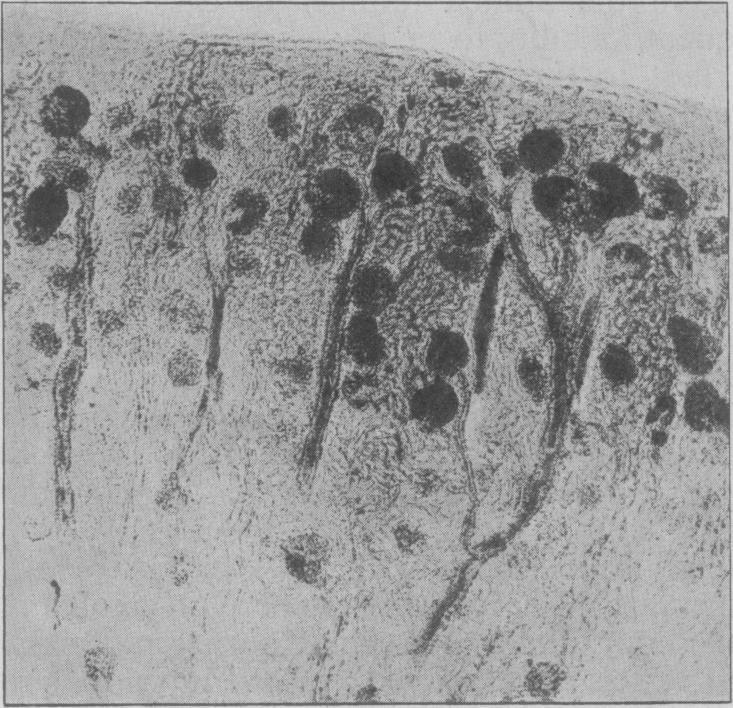

Discussion on the pathological features of cortical necrosis of the kidney and allied conditions associated with pregnancy.

Proc R Soc Med. 1949 Jun;42(6):375-87. doi: 10.1177/003591574904200601.